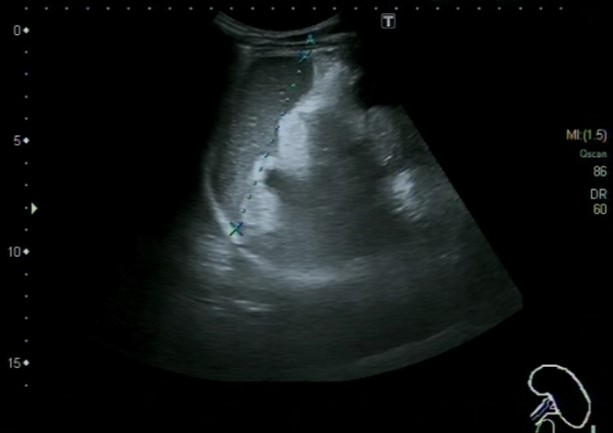

Ecografía abdominal, en la que se identifica abundante cantidad de líquido libre intraperitoneal, a nivel perihepático, periesplénico e interasas, sugestivo de asticis. Hígado, bazo, vía biliar, riñones y vejiga normales.